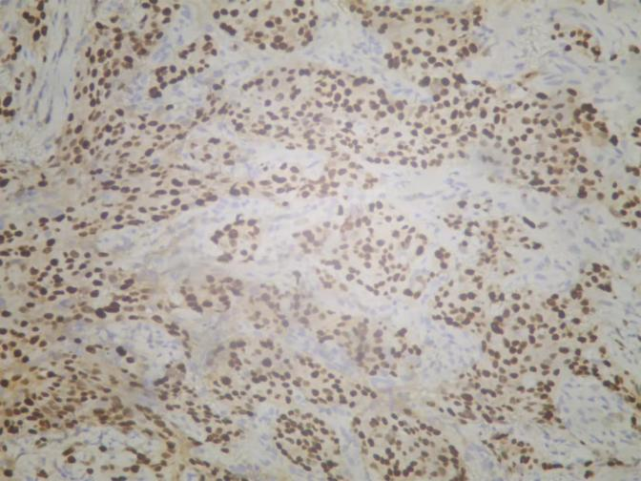

2020-11-06我院行左腋窝淋巴结穿刺活检术,术后病检示:“左腋窝淋巴结”浸润性癌,组织学Ⅲ级

免疫组化结果:ER(中-强+,约80%),PR(强+,约90%),Cerb-B2(3+),Ki67(+,约40%)

图3. 免疫组化Cerb-B2